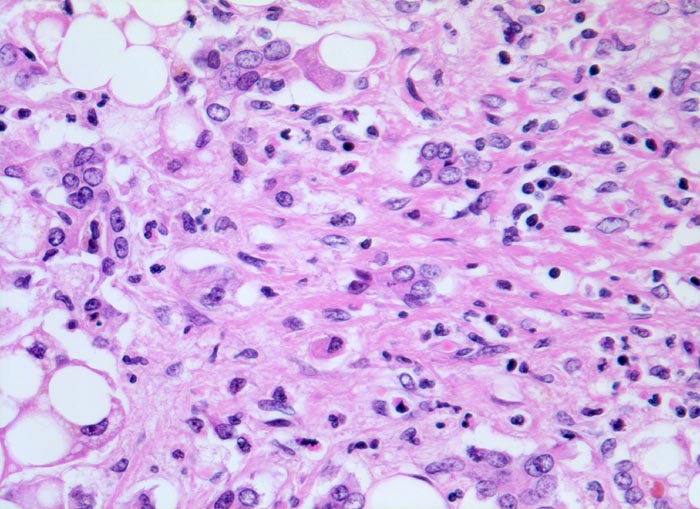

Die Steatose ist der früheste und häufigste pathologische Leberbefund ( 3260) und findet sich bei bis zu 90% der chronischen Alkoholiker. Nach Alkoholkarenz ist sie innerhalb von 3-4 Wochen reversibel. 20-40% der chronischen Alkoholiker entwickeln eine alkoholische Steatohepatitis (ASH). Die Steatohepatitis ist gekennzeichnet durch Schwellung und Ballonierung der Leberzellen, Nachweis von Mallory-Körperchen ( 4947), Apoptosen, perizelluläre Maschendrahtfibrose ( 4950) und überwiegend aus neutrophilen Granulozyten ( 4948)( 4949) bestehenden Entzündungsinfiltraten. Die Veränderungen sind bei Alkoholkarenz rückbildungsfähig. Bei etwa 50% der Patienten mit Steatohepatitis entwickelt sich eine Leberzirrhose ( 1095).

Floride sklerosierende alkoholische Steatohepatitis: Grobtropfige Verfettung von ca. 50% des Parenchyms.Neutrophile Granulozyten umgeben einzelne Hepatozyten (Satellitose). Wenig Apoptosekörperchen. Zahlreiche Mallory Körperchen und Megamitochondrien. Perivenuläre Maschendrahtfibrose.